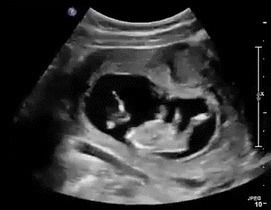

再加上孕肚变大,会挤压到胃部空间。因此孕妈妈的胃口没有那么大,尤其是到了孕晚期。孕妈妈最好的进食方式就是少食多餐,一顿不要吃太饱。如果孕妇感到饥饿的话,多半是之前摄入的食物已经被消化完了,胎宝正在等着“投喂”。2)胎动减少:可能胎宝饿到不想动胎动是一个能够检测胎宝活力的标准。如果平时在这个时间段,胎宝很是活跃,但是某天胎宝却反常地没有怎么活动,那就很可能说明胎宝饿了。

胎宝和大人一样,有能量就喜欢动起来,没有能量便直接躺着不动了。孕妈妈一定要密切感受着小宝贝的一举一动,毕竟这时候只有孕妈妈能够帮上忙。3)胎动频繁:胎宝活动“抗议”除此之外,胎宝的反常举动也要引起孕妈妈的注意。如果你的宝宝平时是个安静的孩子,可是现在却开始剧烈活动,那也可能说明他感到饿了,于是用自己的方式发起反抗。